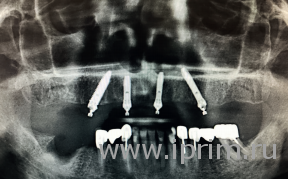

Но обо всем по порядку. Прежде несколько слов о самой технологии. Пятнадцать лет назад Паоло Мало рассчитал, что для того, чтобы протез челюсти выдерживал все нагрузки, достаточно всего четырех, а в отдельных случаях – шести опор. Но установлены они должны быть особым образом. Первые два во фронтальной части челюсти, привычным способом, перпендикулярно линии прикуса. Однако в боковом отделе слева и справа они устанавливаются под углом 30–45 градусов. Это позволяет равномерно распределить нагрузку на все имплантаты.